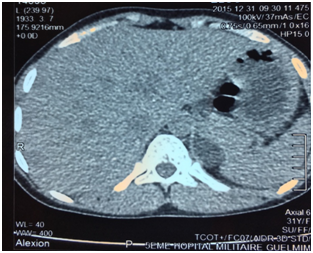

E.O. was a 31-year-old female, with a history of celiac disease under gluten-free diet, and a pregnancy-induced hypertension one year ago, without having been screened for secondary hypertension, to the best of our knowledge. A satisfactory blood pressure (BP) has been reached under treatment with nicardipine (100mg/day). The patient was admitted to our hospital because of headache, muscle weakness and heart palpitations, for two weeks. On physical examination, the patient was in regular general condition and with a healthy coloring. Her weight was 53.5 kg and height 162 cm (BMI=20.41Kg/m2). Blood pressure measured with a manual armlet 190/110 mmHg, heart rate 100beats/minute and regular, respiratory rate 18cycles/min, body temperature 36.9°C. On auscultation, her lungs were clear with no rales. Her heart auscultation showed regular cardiac rhythm with cardiac sounds of normal intensity and no murmurs. Her lower limbs showed symmetric palpable pulses and no edema. The power and sensation of both lower and upper limbs were normal. The abdominal examination showed hydro-aerial noise, no visceromegaly and no abdominal murmur. Thyroid gland examination was normal. There was neither obesity nor hirsutism. Other physical examination was normal. Laboratory findings were as follows: serum potassium 1.68mEq/L (normal range (NR)= 3.5-5.1), sodium 143 mEq/L (NR=136-145), alkaline reserve 32mEq/L(NR=22-31), corrected calcium 95mg/L(NR=86-100), phosphorus 29.9mg/L (NR=25-45), urea 0.15g/L (0.13-0.45), creatinine 3.9mg/L(NR=5-9). The complete blood count and coagulation indices were normal. The thyroid function test was normal (0.94mU/L; NR=0.27-4.2). The measurements of sodium and potassium in the 24-hour urine were 54mEq/L (NR=54-190) and 63 mq/L (NR=25-125), respectively. The ECG showed presence of changes of hypokalemia, U waves and no hypertension changes. Echocardiography assessment of hypertension was negative, and there was no hypertension retinopathy. She was treated with boluses of intravenous potassium chloride and oral potassium supplements, for 260 mmol/day over 6 days. Initially her hypertension was treated with intravenous nicardipine utilizing an electrical syringe pump. Despite intravenous and oral potassium supplementation, her serum potassium level remained low. The PA was suspected because of persistence hypokalemia in association with hypertension and alkalosis. However, after correction of serum potassium level, the patient was examined for the plasma aldosterone concentration (PAC) and direct rennin concentration (DRC). Results revealed a low DRC level of 0.9mUI/L (NR=2.8-39.9), along with a very high PAC level of 2613pmol/l (NR=83-405). The aldosterone to rennin ratio (ARR) was 523pmol/l per mUI/l (N<64). Subsequently, after a three-day oral sodium load, 24-hour urine was tested for the concentration of sodium (260mmols) and aldosterone (27.3mg). Abdominal computerized tomography (CT) revealed a 28x21 mm hypo-dense mass (1UH of density), not enhanced by the contrast product, over the left adrenal gland (Figures 1) (Figures 2). After using spironolactone 100 mg/day and nicardipine 150 mg/day for one month preoperatively, the BP normalized (BP=125/85 mmHg), the headache, weakness and heart palpitations significantly improved, and the serum level of potassium was 4.5 mEq/L. Therefore, the patient underwent a successful laparoscopic left adrenalectomy (Figure 3), and the postoperative course was well. The macroscopic tumor consisted of an ovoid piece of yellow color tissue with weight: 28gr, circumscribed mass: 20x30mm in dimensions adjacent to adrenal tissue. Histologically, the adrenal mass showed an encapsulated epithelial neoplasia with cells of clear cytoplasm, round nuclei and conspicuous nucleoli. However, necrosis, capsular invasion and atypical mitosis were not found (Figure 4). The anatomic pathological diagnosis was adenoma of the adrenal gland consistent with Conn’s adenoma. The patient was normotensive and serum potassium was 4.5mEq/L without any antihypertensive medication or supplement for the last three months after discharge. She was stable with a optimal control of blood pressure without hypokalemia with a 2-year follow-up.

PA is the cause of approximately 0.05-2% of all secondary arterial hypertension is characterized by suppressed plasma renin activity and hypokalemia.3 Conn estimated the prevalence of the disorder around 10% of the general population.4 PA includes unilateral adenoma (=APA) (30%), unilateral (2%) and bilateral (60%) adrenal hyperplasia, familial aldosteronism (1%) and adrenal carcinoma with aldosterone hyper secretion (<1%). The uncontrollable synthesis of aldosterone leads to increased sodium reabsorption, kaliuresis and renin suppression. All of the above challenge arterial hypertension, which affects target organs (heart, kidneys, brain) more gravely than essential hypertension does.5 The APA is a small nodule (< cm) that mostly occurs in the left adrenal gland commonly found in females, and usually present with severe hypertension and more profound hypokalemia. It is also more common in younger patients (30-50 years of age), with higher plasma and urinary levels of aldosterone.6 Some patients are completely asymptomatic or have minimum symptoms resulting from hypertension (headache) and hypokalemia (polyuria, nocturia, muscle cramps). Occasionally, excessive muscle weakness, paresthesias, tetany, and even muscle paralysis may occur.2,7,8 Usually, PA is characterized by hypertension, hypokalemia, excessive urinary excretion of potassium, hypernatremia, and metabolic alkalosis.7 It is recommended testing for the PA in the following groups: patients with hypertension and hypokalemia, treatment-resistant hypertension (three antihypertensive drugs and poor control), severe hypertension (>160 mmHg systolic or>100mmHg diastolic), hypertension and an incidental adrenal mass, and onset of hypertension at a young age.6 We described a case of young (31 year-old) female with a pregnancy-induced hypertension one year ago, without having screened for secondary hypertension, and with satisfactory control of blood pressure under treatment with nicardipine, which favors the initial diagnosis of controlled primary hypertension, despite its beginning at an age suggesting secondary hypertension. The occurrence of hypertension crisis with headaches, muscle weakness, heart palpitations, and significant hypokalemia led us to consider a cause of hypertension secondary in origin superimposed on primary hypertension. Despite intravenous and oral potassium supplementation, her serum potassium level remained low. The PA was suspected because of persistence hypokalemia in association with severe hypertension and alkalosis. Hypokalemia (serum potassium ≤3.5mmol/l) is only present in a minority of patients with PA.9 However; the frequency of hypokalemia is related to whether PA can be surgically cured. A study with a large series of patients reported that hypokalemia was present in 7%, 17% and 48% of patients with essential hypertension, idiopathic PA, and APA, respectively.10 Our patient had an association of PA secondary to APA, and celiac disease under gluten-free diet. This association has never been described in the literature. Both diseases can manifest as hypokalemia, PA by excessive urinary excretion of potassium, and celiac disease by mal absorption, which could trigger or aggravate hypokalemia. The diagnostic approach of PA can be consisted in three steps: the ARR calculation, confirmatory tests of PA and distinction of the disease subtypes. Recent guidelines suggest screening for PA patients with difficult-to-treat or hypokalemic hypertension using the ARR.9 The ARR was introduced by K Hiramatsu and colleagues in 1981 as a screening tool to facilitate the diagnosis of PA among hypertensive patients.11 Although, using the ARR decreases the intra- and inter-patient variability in renin and aldosterone levels linked to sodium intake, body position and age.12,13 The most frequently used cut-off values for PAC to PRA ratios are in the range of 20 to 50ng/dl (554 to 1.385pmol/l) per ng/ml.h; for PAC to DRA, these values are in the range of 2.4 to 4.9ng/dl (66 to 136pmol/l) per mU/l.14 Our patient had a two ARR greater than 136pmol/l per mUI/l. The recent clinical practice guidelines for case detection, diagnosis, and treatment of patients with PA recommend that patients with positive ARR undergo any of four suppression tests to confirm or exclude the diagnosis of PA.14This implies that PA is defined as a non-suppressible aldosterone excess. The four suppression tests respectively use oral sodium loading, oral fludrocortisones, oral captopril, or saline infusion to suppress aldosterone secretion.9 Oral sodium load test includes the determination of sodium and aldosterone concentration in 24-hour urine, after 3 days of increased salt intake. Rates of aldosterone >12mg and sodium>200mmols are diagnostic of PA.6 This test confirmed the presence of PA in our patient (Aldosterone: 27.3mg/24h, Sodium 260mmols/24h). We did not proceed to saline infusion test (intravenous infusion of 2 liters of saline in four hours leads to a PAC rate over 277pmol/l if PA is present), oral captopril test and fludrocortisones test. The fludrocortisones suppression test is rarely performed in most centers nowadays.6 Distinction of disease subtypes is based on CT, adrenal vein catheterization with venous sampling and genetic screening for the familial types of the disease.14 In our patient, abdominal CT demonstrated a 28x21 mm hypo-dense mass (1UH of density), not enhanced by the contrast product, over the left adrenal gland. Unenhanced attenuation values on CT<10 UH indicated adenoma, as carcinoma present with values over 10 HU.15 The presence of an adenoma in patients with PA suggests the presence of an APA, but it cannot exclude the combination of a non-secreting adenoma and idiopathic PA.14,16 For distinction of the disease subtypes, a more practical approach use for the adrenal vein sampling (AVS) as recommended by Young.6 which is based on patient preferences, age, adrenal morphologic appearance on CT, clinical comorbid conditions, and clinical probability for finding an APA. For patients younger than 40 years, in whom a solitary adenoma is >1cm with normal contralateral adrenal gland, a unilateral adrenalectomy may be done without AVS and in the absence of comorbid conditions. Therefore, the AVS was bypass in our case based on these criteria.